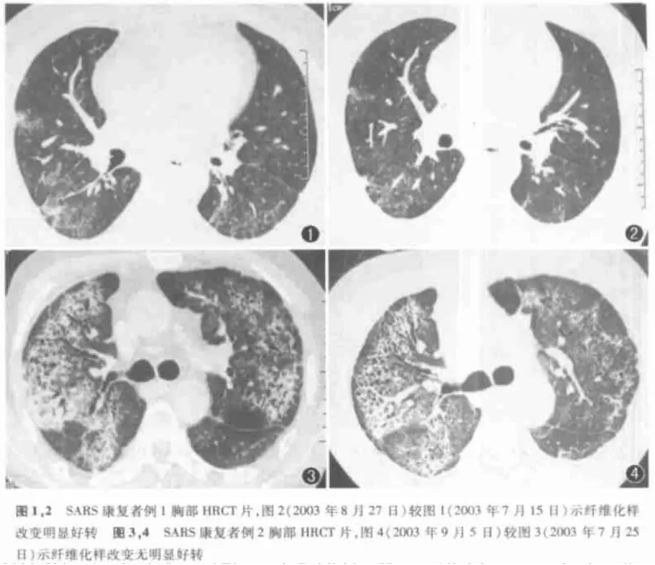

不同康复者的肺部HRCT图象,可以看出肺部纤维化有无的明显区别 | 图源:解立新等

轻症患者一般不会有肺纤维化,但对于重症患者,他们经历的治疗疗程更长,也更容易产生“免疫风暴”。肺纤维化的可能性和严重程度也更高。(一般在入院后40天左右会发生肺纤维化)

出院的判断标准主要是根据体温、呼吸和胸部X射线观察,很多患者其实还留有肺纤维化的隐患出院。

虽然查到的很多报道都表示,SARS导致的肺纤维化比较特殊——随着时间的推移,肺纤维化会有好转,但这个过程可能需要非常久,很多研究只有短短一年,并不能看出什么效果。